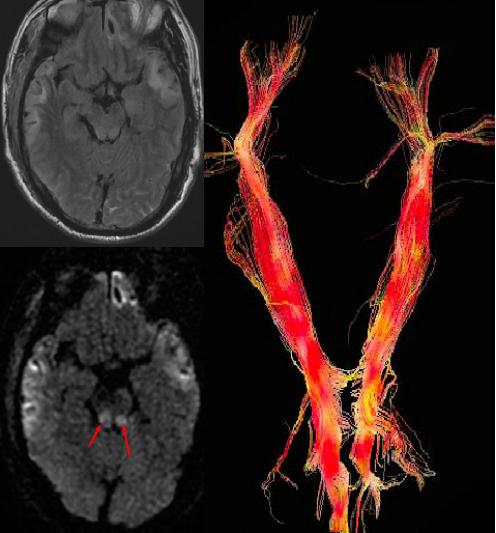

脑血管病应用

我们知道,DWI有助于超早期、早期脑梗死的及时诊断,而DTI在检测脑梗死后神经纤维束的损伤方面有着显著优势。

不同时期脑梗死的ADC和FA值均会有不同的变化:在超急性期病变区ADC值降低,FA值轻度增高;在急性期病变区ADC值、FA值均比对侧相应部位降低;亚急性期FA较健侧有明显下降,ADC 值变化不一致;慢性期病变侧较健侧FA值持续降低而ADC值高于健侧。FA值的变化与缺血损伤的严重程度有关,A值的水平还可以反映细胞肿胀、胞膜降解的程度,即缺血性损伤的严重程度。

DTI也可显示血肿、梗死区与纤维束的关系,如接近、穿行、中断等,有助于判断白质纤维束损害程度与身体相应部位的功能障碍的关系,有助于判断临床治疗效果、判断病人恢复、预后。

右侧基底区急性期梗死FA值下降,纤维束局部中断

此外,有学者研究发现,与梗死区相联系的同侧内囊、大脑脚和桥脑处的皮质脊髓束FA较对侧显著降低,提示脑梗死后远端的皮质脊髓束可能存在进行性的Wallerian变性,通过对梗死远端皮质脊髓束FA计算判断其变性程度,可以预测患者的运动功能转归。

脑外伤的应用

弥漫性轴索损伤的患者中,绝大多数都会表现出弥散各向异性程度的改变。外伤后弥漫性轴索损伤最初的24小时里,在普通MR上表现正常的白质可能会出现弥散各向异性指数轻度的下降。而外伤几周后这种下降会很明显。

外伤患者DWI显示脑干损伤,DTT图示白质纤维束扭曲变形及移位

此外,对于一些脑挫裂伤的患者,DTI也可显示挫伤区与纤维束的关系,同样有助于判断白质纤维束损害程度与身体相应部位的功能障碍的关系,有助于判断临床治疗效果、判断病人恢复、预后。